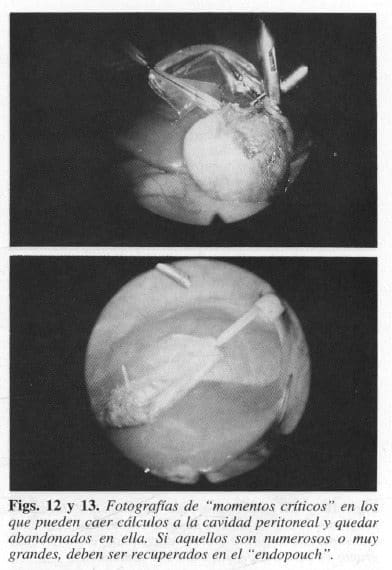

Además, continuamos en el análisis riguroso de la técnica quirúrgica de la colecistectomía laparoscópica y en la identificación de los que, a nuestro juicio, hemos denominado “momentos críticos”, esto es, aquellos en los que pueden caer cálculos biliares en la cavidad peritoneal. Proponemos así recursos y soluciones para evitar tales eventos.

Si los cálculos esparcidos son muchos o muy grandes, deben ser recuperados primero en el endopouch (Figs. 12 y 13).